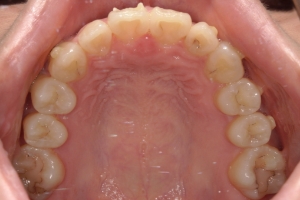

BEFORE

治療前

PROCESS

半年

AFTER

治療後

下の前歯が上あごの歯ぐきに当たるほど噛み合わせが深く、そのことが原因で上顎歯列の正中にすき間(正中離開)が生じていました。部分矯正ですき間を無理やり閉じても、噛み合わせが深いままでは治療後の再発リスクが高くなります。そのため全体矯正で奥歯の噛み合わせを整え、噛み合わせを浅くしつつ前歯を並べました。正中離開は戻りやすい傾向があるので、再発を防ぐため固定式リテーナーを推奨しています。